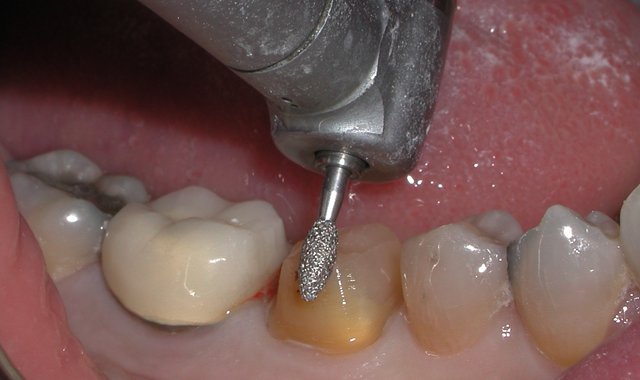

Fig. 1

A 60-year-old male patient presented complaining of pain from the lower right first molar. Upon clinical examination, tooth #30 was sensitive to percussion and had a fractured disto-occlusal-lingual amalgam.

After discussion with the patient and effective local anesthesia, the existing amalgam was removed to reveal caries extending into the pulpal tissue (Fig. 1).